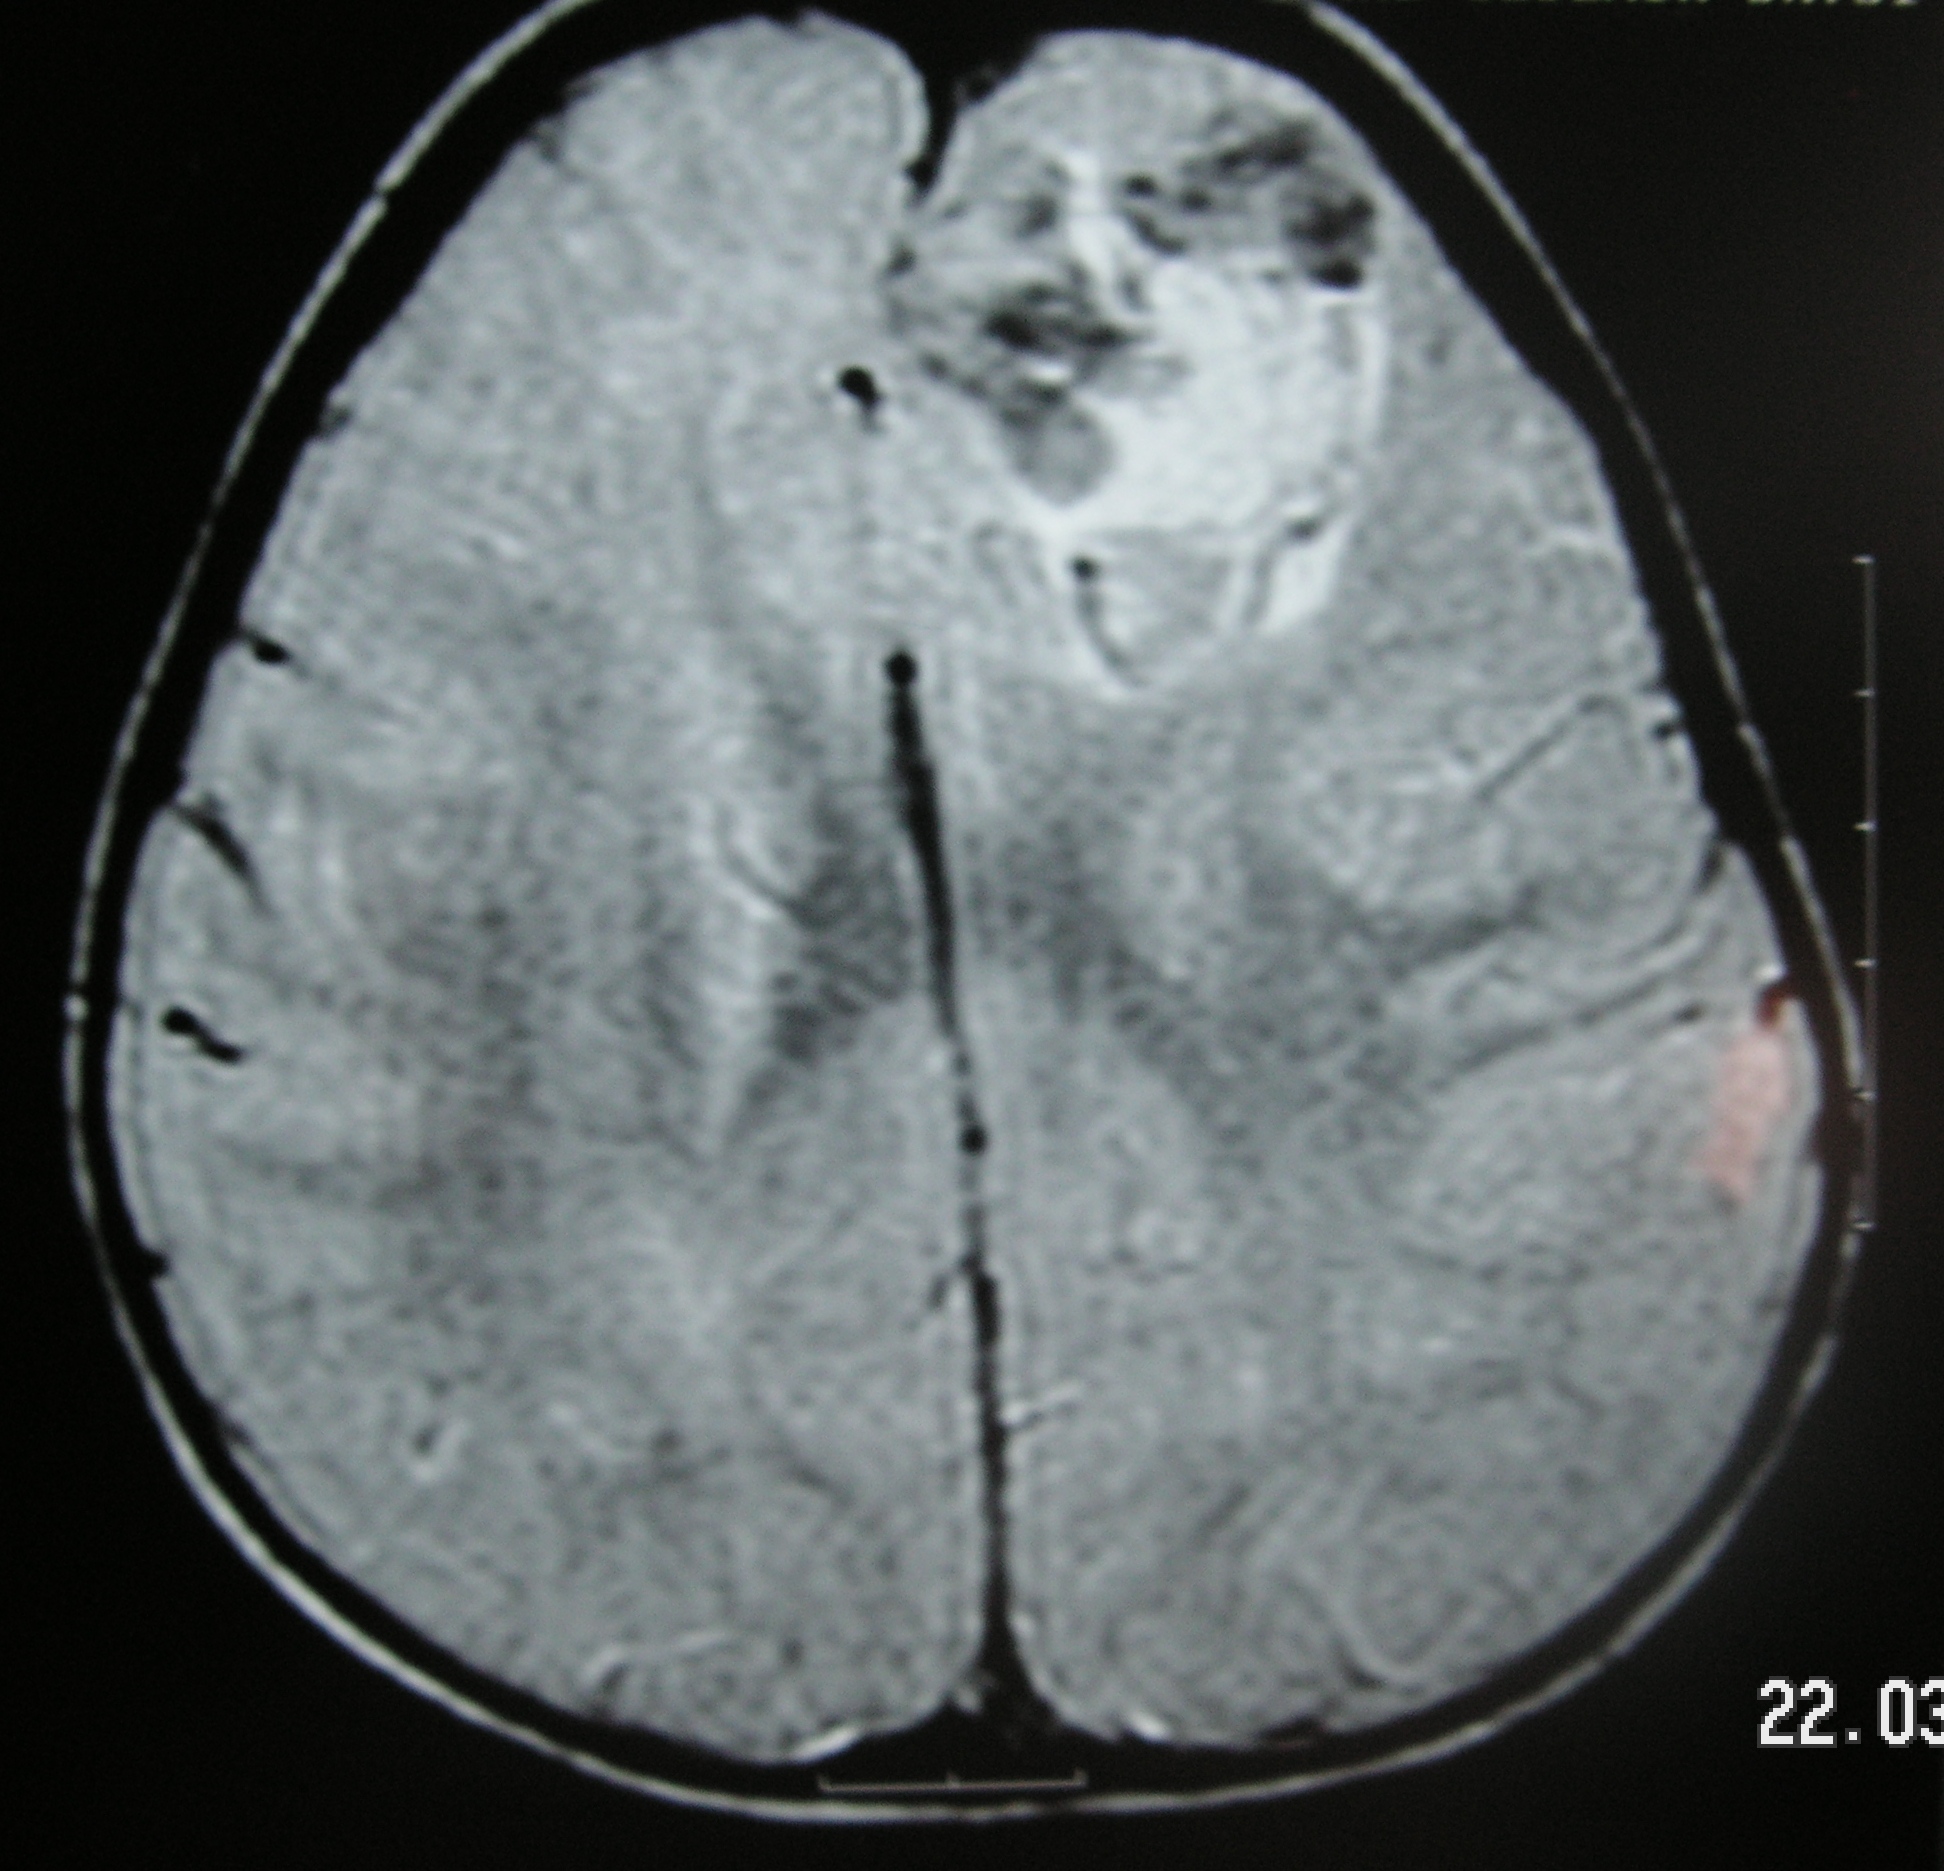

Beyinde bir atardamar tıkanmışsa genellikle beyinde kanama olmaz, o damarın kan götürdüğü doku hasar görür. Beyin toplardamarı yırtlımışsa kanama görülebilir, ancak toplardamar tıkanmışsa bazen kanama ve/veya beyin dokusunda hasar görülmeyebilir.

Bir çocukta ani felç, motor kayıp geliştiğinde zaman geçirmeden çocuk acil ünitesine başvurulmalıdır. Beyin ve beyin dammar görüntüleme incelemeleri ile teşhis konulur, uygun tedavi uygulanır, altta yatan sebep araştırılır.